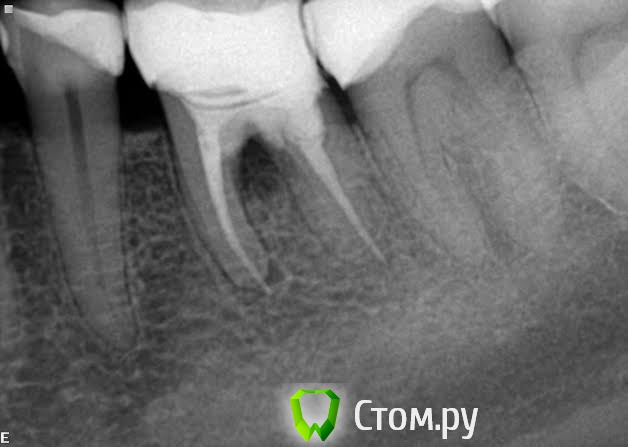

gsp Опубликовано 22 мая, 2014 Поделиться Опубликовано 22 мая, 2014 Вопрос для самообразования: Это из-за затемнения между корнями? Ссылка на комментарий

red_butler Опубликовано 22 мая, 2014 Поделиться Опубликовано 22 мая, 2014 Вопрос для самообразования: Это из-за затемнения между корнями?Деструкция (рассасывание) костной ткани Ссылка на комментарий